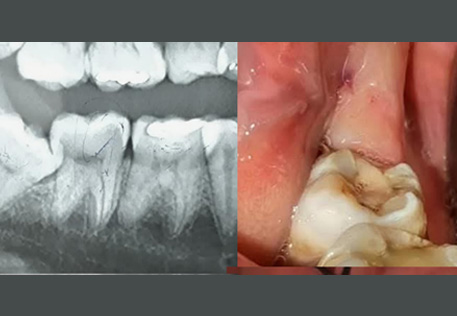

Comprehensive oral examination with digital X-rays to assess the position and condition of your wisdom teeth.

Surgical Extraction: For impacted or partially erupted wisdom teeth, performed with precision by our skilled oral surgeons.

Before / After